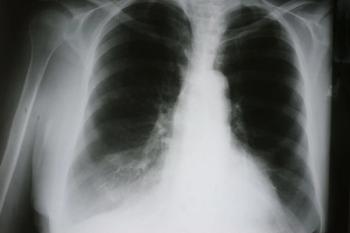

Patients taking nitrogen-containing bisphosphonates have a lower risk of developing and dying from pneumonia after hip fracture compared with patients taking other types of medication for osteoporosis or no drugs for osteoporosis at all, a study published in the Journal of Bone and Mineral Research has found.

Rheumatoid arthritis is not associated with an increased risk of death in patients hospitalized for pneumonia, unless it is uncontrolled, shows a new study.